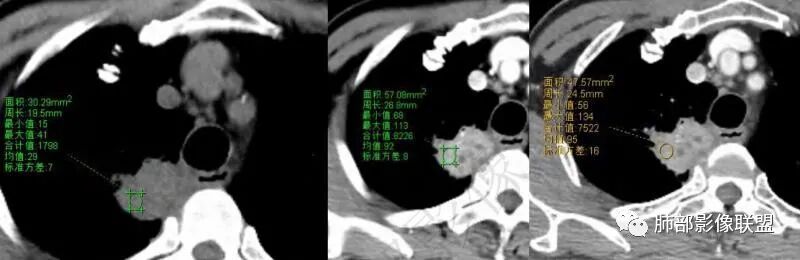

红日初升:老年男性,干咳十天,无发热,血象、肿标不高。右肺上叶团片,叶段分布,边缘多平直凹陷,强化见三层结构,考虑脓肿。边缘局部膨隆,近侧支气管阻塞,恶性不能排除,建议治疗后复查

丽:老年男性,急性病程,右肺上叶团片状高密度影,边缘有膨隆也有平直,胸膜下脂肪间隙消失,增强后明显强化,静脉期持续强化,并见条形低密度影无强化,考虑慢性炎症,建议抗炎治疗后复查除外恶性

爱跳舞的猫:老年男性,干咳,无发热,血象、肿标不高。右肺上叶团片影,呈条状,边缘多平直,增强扫描明显强化,其内见无强化坏死区,内壁光滑,考虑脓肿,建议治疗后复查除外恶性

凝睦:右肺上叶团块,边缘平直,胸膜糊墙,明显强化,内部血管走行自然,支气管粘液栓,考虑炎性。

采莲:老年男性,干咳,有吸烟史,右肺上叶不规则肿块,边缘平直收缩为主,,有细软毛刺,靠近纵隔边缘,明显强化,内有粘液栓,近端支气管阻塞,阻塞端圆盾,无明显胸膜增厚,感觉既有恶性征象,也有良性征象,血象不高,血沉快,肿标不高,但患者有吸烟史,主要是炎症和肿瘤鉴别,首选炎性肉芽肿,鉴别肺癌,毕竟有肺气肿背景,肿瘤不排除。建议穿刺。

王江涛:边缘平直,明显强化,血管穿行,部分支气管扩张积液,胸膜糊墙,支持炎性病变,结核不除外。

宇宙:右肺上叶纵隔旁肿块,形态欠规整,边缘平直为主,周围长索条,邻近胸膜增厚,明显强化,血管未见破坏,其内支气管粘液栓,考虑炎性肉芽肿

陈学君:右肺上叶实变灶,边缘平直为主,胸膜糊墙,强化较明显,似有支气管粘液栓,考虑慢性炎症。

红星:老年男性患者有长期的吸烟的病史,临床症状是干咳。影像学表现右上肺胸膜下的分叶状的结节,密度欠均,内部见小灶性的坏死以及支气管空泡征,增强扫描呈明显的强化,从重建的图像来看,病灶的上下径较长,并沿着支气管的长轴生长,纵隔内无明显的肿大淋巴结。考虑肉芽肿性病变,结核性病变?炎性?鉴别诊断:肺鳞癌。

秦化君:老年男性 刺激干咳,右肺上叶纵隔胸膜下不规则软组织密度团块影。边缘部分膨隆、凹陷,可见分叶、毛刺。矢状位似可见支气管堵塞截断。肿块相邻胸膜栽桩,似侵及气管壁(刺激性干咳的原因)。增强后中等以上强化,内见条状无强化影(粘液栓?)。综合考虑恶性病变可能大。炎性肉芽肿待排。

放射线:右肺尖不规则肿块,有分叶毛刺,有胸膜栽赃,冠状位可见支气管粘液栓,矢状位病灶呈外朝内沿支气管分叉角生长,强化明显,考虑腺癌,鉴别炎性肉芽肿病变。

旁观者:老年男性,长期大量吸烟,刺激性干咳,无发热及胸痛,感染指标及肿瘤标记物阴性,影像,右肺上叶靠近纵隔长条状病灶,边缘收缩,长毛刺,明显强化,见粘液栓,支气管情况不好评估,无磨玻璃及树芽,纵隔淋巴结不大且无钙化,胸水无。建议支气管镜排除气道占位性病变,或者外朝内病变,结核或者腺癌,感染性病变OP伴脓肿,老年,吸烟,首先排除癌

飞鹰行动:老年男性,咳嗽入院,影像表现右肺上叶实变病变,局部边缘平直凹陷,与胸膜相贴,未见胸膜牵拉,近端支气管壁增厚,支气管进入病灶后阻塞,增强病灶强化较明显,内见支气管粘液栓,考虑慢性炎性病变,结核不排除。

周太狼:老年男性,吸烟,急性病程,右肺上叶团片状高密度影,边缘收缩膨隆,长毛刺,增强后明显强化,内见少许条形低密度影无强化区,支气管似有阻塞,考虑慢性炎症,建议抗炎治疗后复查除外肿瘤病变

衡妈:老年男性,右肺上叶尖段沿支气管走形片状实性密度,平扫密度相对均匀,横断面显示有明显平直、凹陷边,与周围肺野界限清晰,少许长软毛刺,与侧胸膜宽基底相连,未见明显支气管堵塞;增强后明显延时强化,强化不均匀,可见小灶性坏死,所见纵隔未见肿大淋巴结。考虑慢性炎性病变,炎性肌纤维母细胞瘤?鉴别腺癌。

小兜:老年男性,既往吸烟史,刺激性干咳十余天入院,血象及肿标未见异常。CT示右肺上叶脊柱旁不规则实变影,平扫密度较均匀,增强扫描呈渐进性明显强化,内部可见粘液栓。支气管进入病灶后狭窄阻塞,综合考虑为炎性病变

了:右肺上叶肿块影,边缘清楚,纤维条索影,均匀强化,内可见低密度坏死影,考虑慢性炎性肉芽肿

看图说话:右肺上叶团块状影,气管堵塞,边缘膨隆,密度不均,内见坏死,粘液栓,胸膜栽赃,增强后明显强化,考虑慢性炎症,鉴别腺癌。

安吉木子何方李:良恶性征象都要,感觉支气管鼠尾样狭窄,明显强化,还是先考虑恶性肿瘤。患者有支气管粘液栓,无强化,炎性肉芽肿需要考虑

?????天涯?????:内有小片状低密度影,强化这么显著,大概又是个肉芽肿性炎或脓肿之类的,建议抗炎治疗后复查,除外恶性肿瘤性病变鳞或腺癌可能。

信人生:老年男性,急性病程,右肺上叶尖后段团片状高密度影,明显桃尖征象,胸膜下脂肪间隙消失,增强后明显强化强化值约60HU,静脉期持续强化,并见条形低密度粘液栓,化验肿标及结核抗体均阴性,白细胞不高,考虑炎性肉芽肿/慢性炎症,建议抗炎治疗